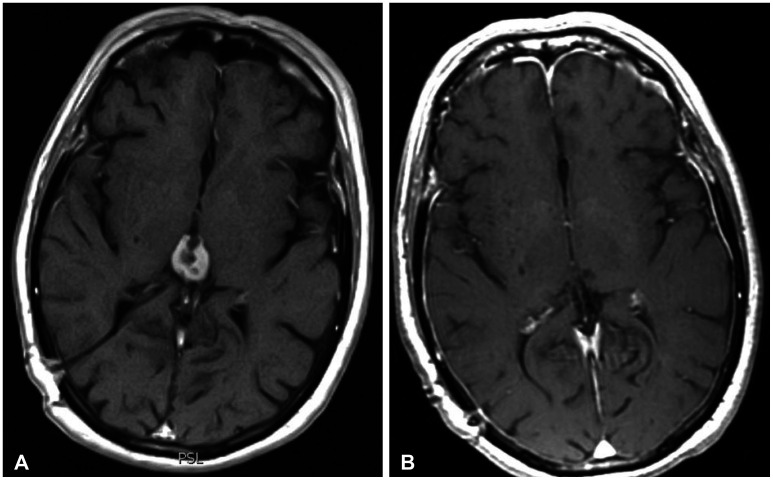

Abstract Image